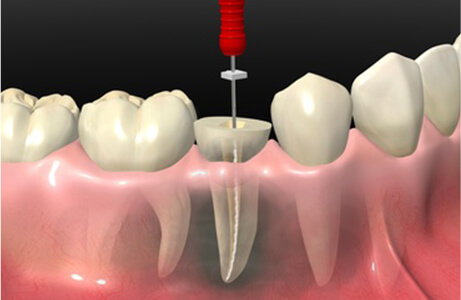

根管治療は、むし歯が歯の神経まで達した場合に、抜歯せず残すために行う治療です。

むし歯菌に侵された神経を取り除き、根管内の殺菌消毒を行います。

根管治療は一度の通院で治療が終わらないため、患者様のご協力が必要となります。

ご自身の大切な歯を守るためのお手伝いをいたしますので、根気強く治療を続けていきましょう。

何かご不明点やお悩みがあれば、お気軽にお尋ねください。